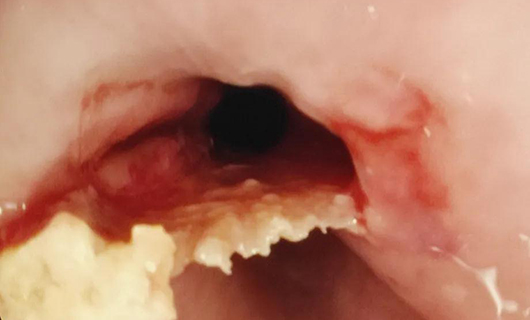

PART3:上切开刀“啃”下硬骨头

小明(化名)一吃东西就“胸痛”,胃镜显示,食道中下段有异物,是一块呈倒三角形的骨头,而且嵌入太深,异物钳夹取失败,鼠齿钳也“啃”不动这块骨头。边鹏想到了切开刀,用调到最高频率的切开刀在骨头最宽处一点一点切出一个豁口,在切开刀作用下,骨头变得松软,豁口处合上时,卡着的骨头松动了,再用异物钳将骨头夹出。